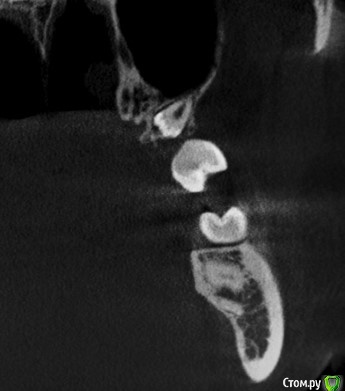

Дмитрий М Опубликовано 9 ноября, 2020 Поделиться Опубликовано 9 ноября, 2020 28,38 без особенностей29 под костным, повернут коронкой в небную сторону, нежно аккуратно, чтобы не протолкнуть в пазуху, удалял в зеркало 4 Ссылка на комментарий